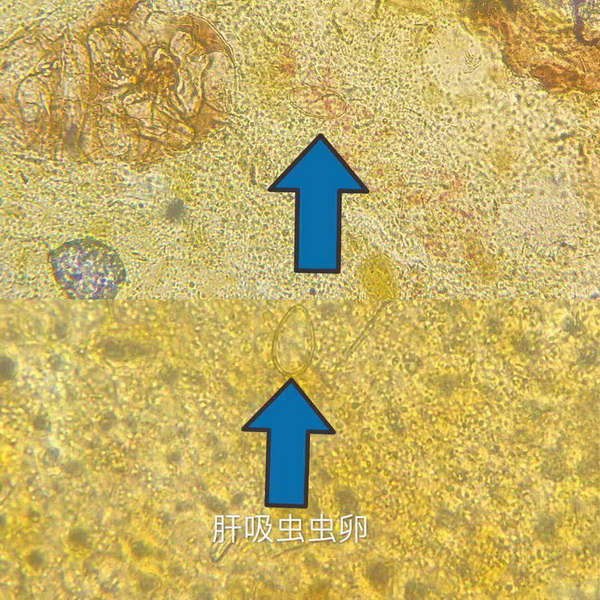

图4、显微镜下的肝吸虫虫卵